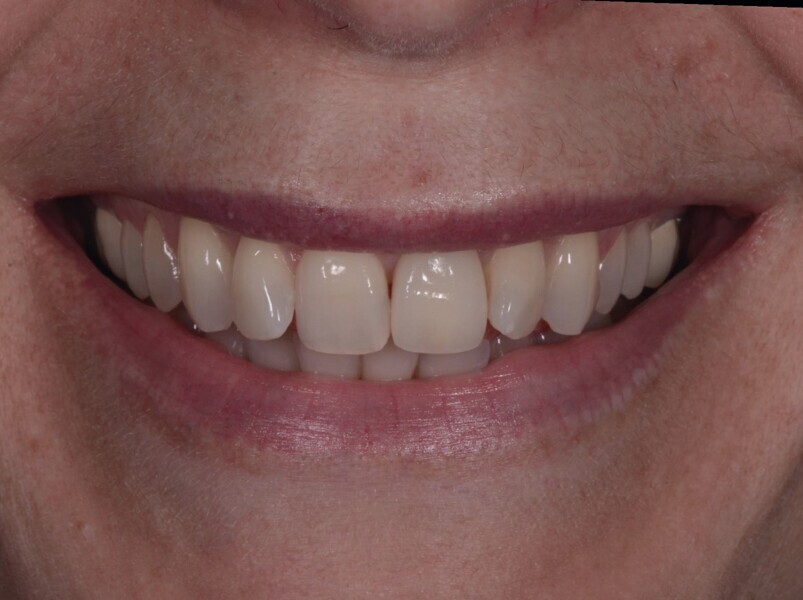

Fig. 21a : Sourire avant le traitement.

Fig. 21b : Sourire après le traitement.

Lors du suivi a cinq ans, on ne peut que constater le résultat esthétique maintenu (Fig. 21). La radiographie montre un niveau osseux stable et une connexion étroite entre l’implant et le pilier (Fig. 22).